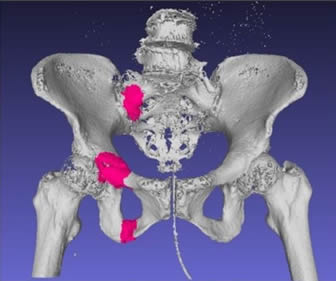

人工知能による骨盤骨折検出アルゴリズムの研究を進めています。高齢者の骨粗しょう症による骨盤骨折は自覚症状が少なく、専門医による診断が行われず見落としが多発しています。この研究で医師不足の地域やクリニック、夜間救急などでの骨折の見落としを防ぎます。将来的には全自動での検出も可能になるかもしれません。